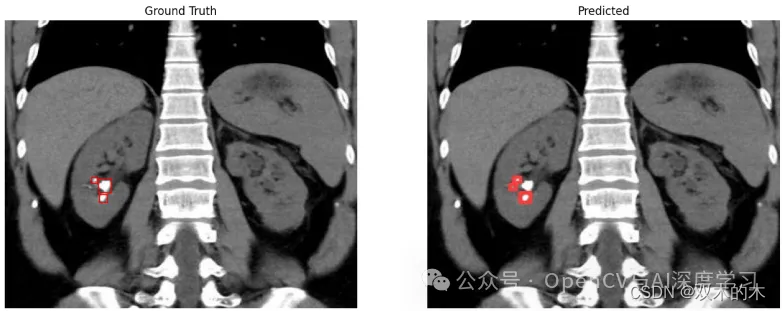

示例三:同一图像中有不同大小的肾结石(漏检+错检)

观察结果:在如上所示的样本中,我们可以观察到同一样本中存在大小和形状各异的肾结石。这对任何检测模型都构成了威胁。在这里,模型未能检测到相对较大的结石。不仅如此,模型还将白色像素伪影误认为是真正的小结石。这同样是不可接受的。